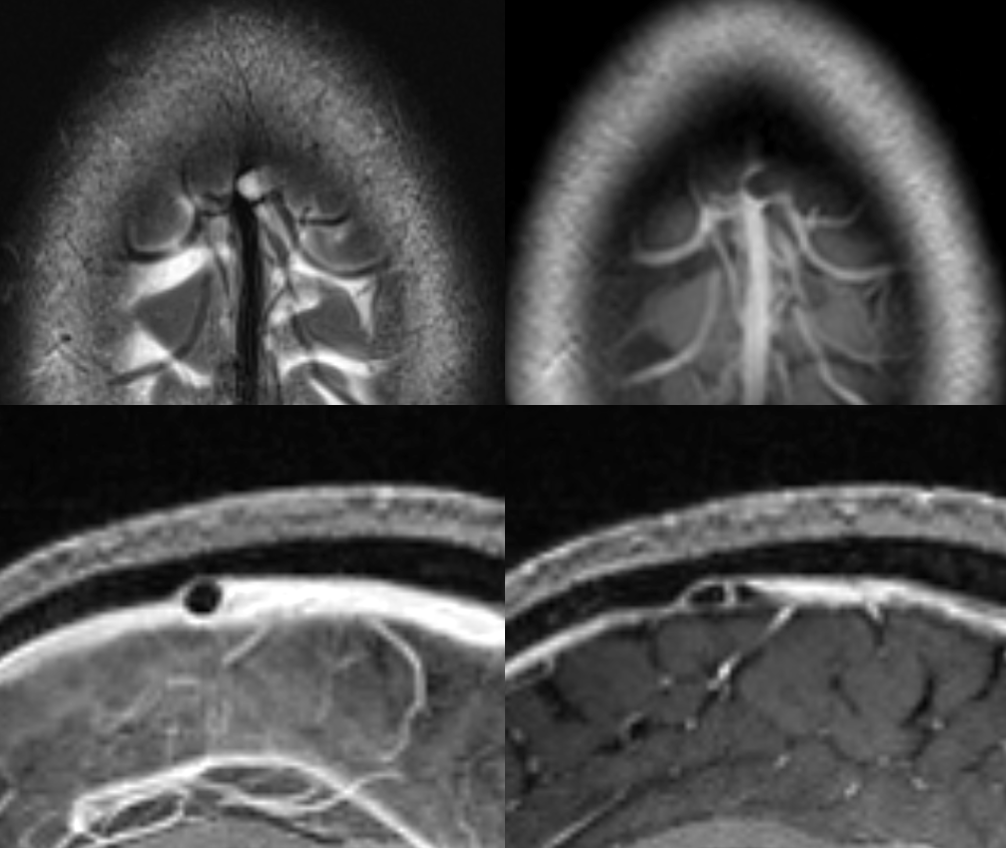

All of the above anatomic knowledge can become very useful in evaluation of venous thrombosis. Numerous collateral pathways develop in this setting attempting to compensate for the loss. The most dramatic cases usually involve the largest channel — the superior sagittal sinus. In this case, a man presented with what initially was thought to be vasculitis-related brain hemorrhage. Subsequent workup led to an angiogram, where sagittal sinus thrombosis with extensive trans-cerebral and trans-osseous emissary vein collateral channels was seen. In retrospect, these findings were present on the patient’s earlier contrast MRI. “Venovibe” or other contrast-enhanced MR venograms can very sensitive, particularly when interpreted with the appropriate index of suspicion. Noncontrast 2-D time of flight MRV I consider to be next to useless as a problem-solving technique. Any thin-slice postcontrast T1 study is vastly superior.

MRI of the same patient shows the characteristic rounded appearance of the cortical vein (light blue arrows), located just medial / deep to the dura (brown arrows), as distinct from the flattened, oval look of the dural sinus (white arrow). The post-contrast high-resolution T1-weighted images are the best way to look for dural sinuses like this one on non-invasive imaging